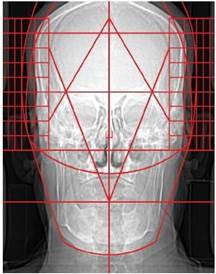

9.5.13. Central Skull Line (CSL) Template

An example of this template is shown below: